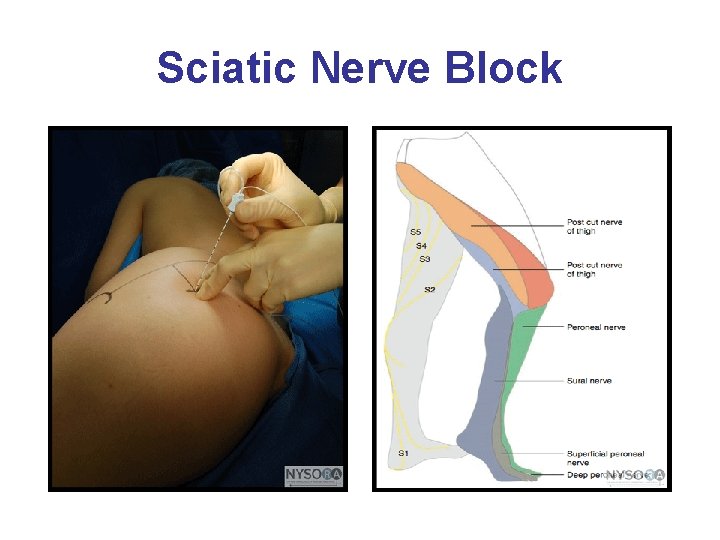

Sciatic Block • The sacral plexus provides motor and sensory innervation to the entire lower extremity including hip, ankle and knee. Important components are the sciatic and posterior cutaneous nerves • Landmarks are the greater trochanter, the posterior superior iliac spine, and the sacral hiatus. • Twitch monitors may be used with the goal of visible or palpable twitches of the hamstrings, calf muscles, foot or toes. • The patient needs adequate sedation; commonly painful. Onset of block usually occurs in 10 -25 minutes. • It provides for complete anesthesia of the leg except for the medial strip of skin innervated by the saphenous nerve. Combined with a femoral block, complete anesthesia of the leg may be achieved. • More discreet posterior blocks are generally used

Sciatic Nerve Block